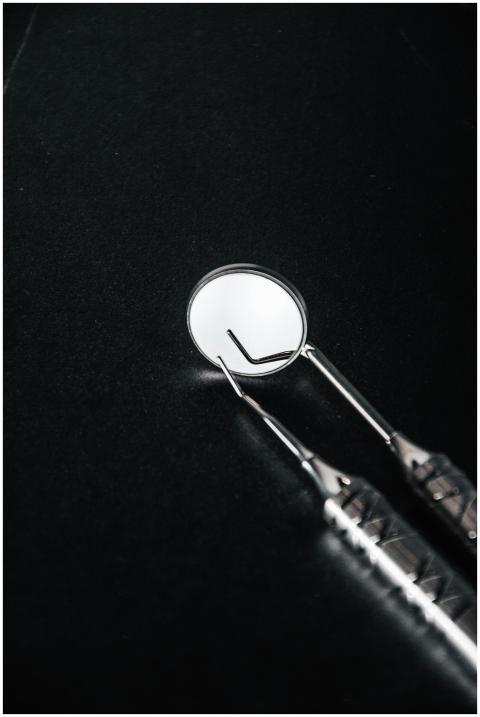

Close-up of stainless steel dental tools on a blac

by Alivia Upton